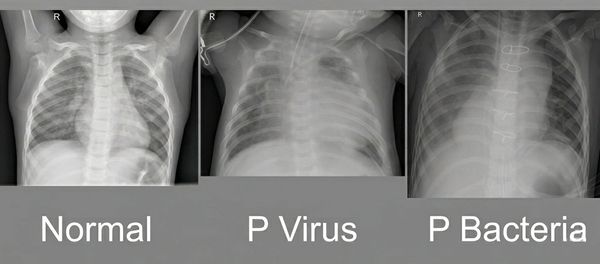

Imaging and machine learning is a new emerging field which may help train doctors and diagnose patients. Current tryouts are quite promising, but further investments are needed to get into the high quality results that human medicine requires. Medical image diagnostics have been tested to diagnose pneumonia and breast cancer, as examples. In pneumonia there are two types of pneumonia, one caused by virus and another by bacteria. Treatments are quite different one from the other so it is important to differentiate them. This technology could help as it is hard to see any difference for the non trained eye.

ML Results to detect and differentiate virus pneumonia and bacteria pneumonia were interesting. The initial model was trained with about 2,700 images and shows its accuracy may improve when more images are used. The dataset was a public dataset.